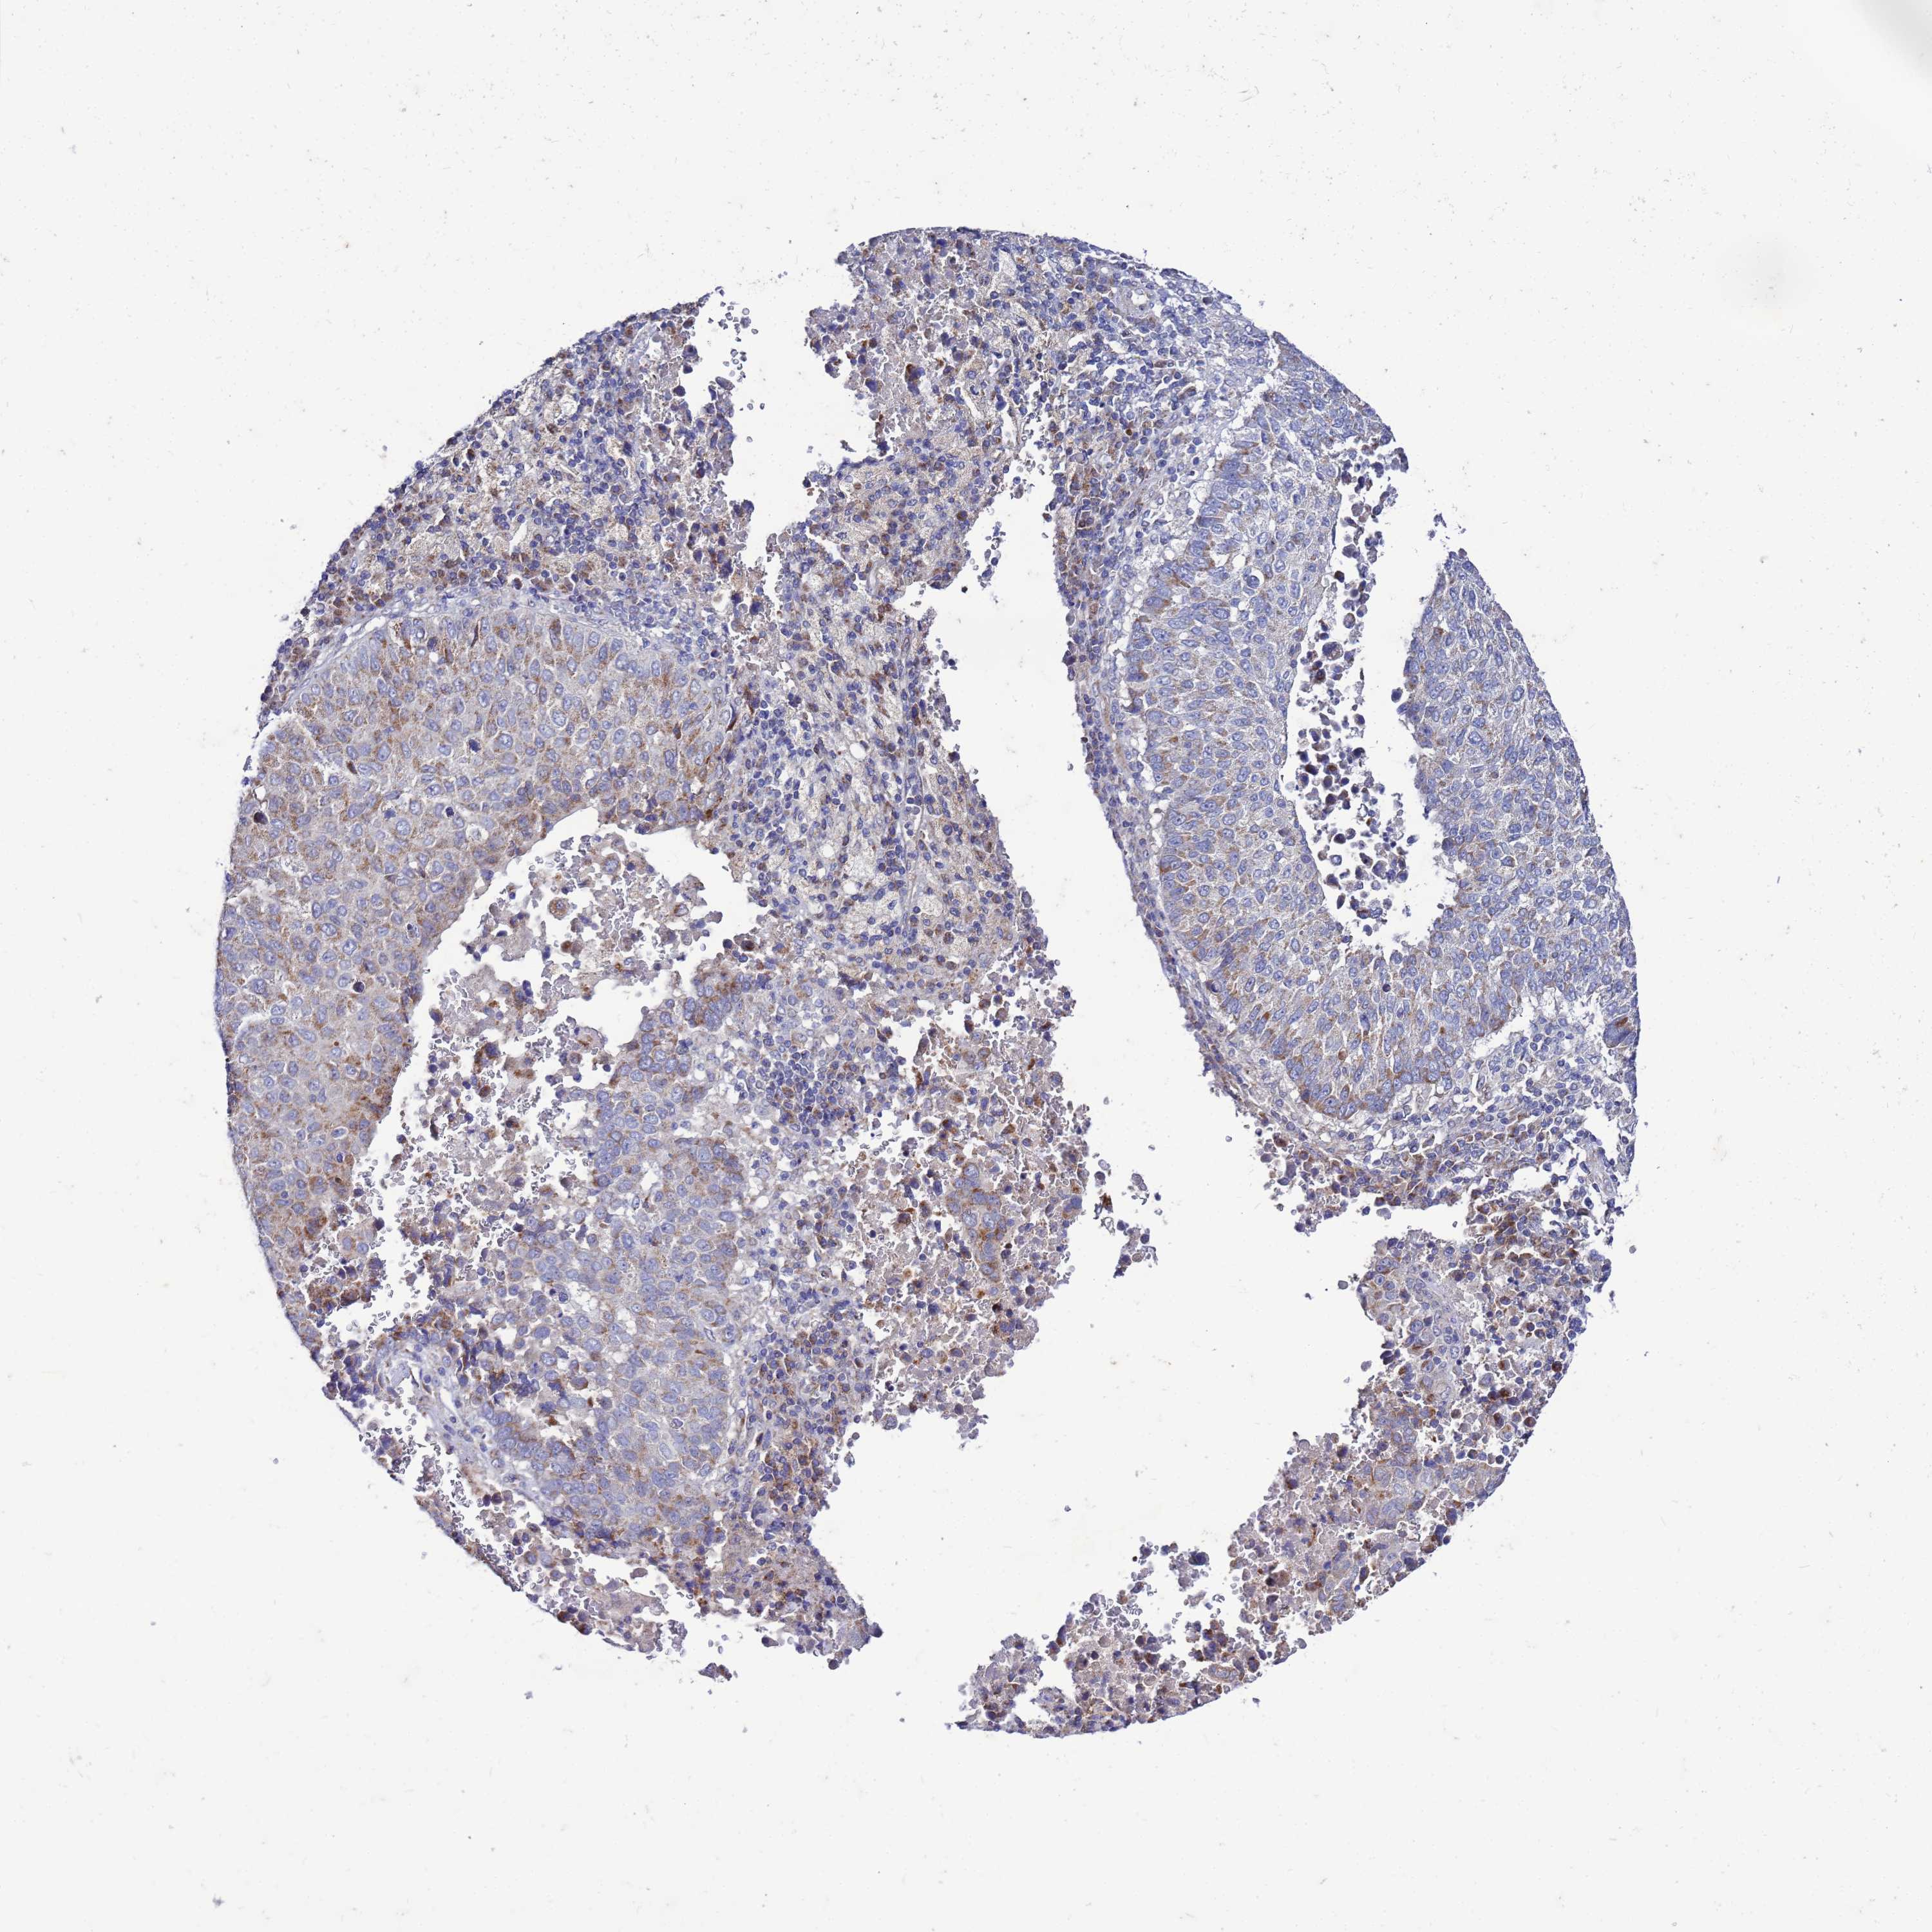

LUNG SQUAMOUS CELL CARCINOMA (TCGA) - Interactive survival scatter ploti

The Survival Scatter plot shows the clinical status (i.e. dead or alive) for all individuals in the patient cohort, based on the same data that underlies the corresponding Kaplan-Meier plots. Patients that are alive at last time for follow-up are shown in blue and patients who have died during the study are shown in red.

The x-axis shows the expression levels (FPKM) of the investigated gene in the tumor tissue at the time of diagnosis. The y-axis shows the follow-up time after diagnosis (years). Both axes are complimented with kernel density curves demonstrating the data density over the axes. The top density plot shows the expression levels (FPKM) distribution among dead (red) and alive patients (blue). The right density plot shows the data density of the survived years of dead patients with high and low expression levels respectively, stratified using the cutoff indicated by the vertical dashed line through the Survival Scatter plot. This cutoff is automatically defined based on the FPKM cutoff that minimizes the p-score. The cutoff can be changed by dragging the vertical line or by entering a cutoff value in the square labeled "Current cut-off".

Under the Survival Scatter plot the p-score landscape (black curve; left axis) is shown together with dead median separation (red curve; right axis). Dead median separation is the difference in median mRNA expression between patients who have died with high and low expression, respectively. It is calculated as follows: median FPKM expression of dead patients with high expression - median FPKM expression of dead patients with low expression. This is intended to aid the user in visually exploring custom cutoffs and the associated p-scores and dead median separation.

Individual patient data is displayed and can be filtered by clicking on one or more of the category buttons on the top of the page. Categories describing expression level and patient information include: high, low, alive, dead, female, male and tumor stages. The scale of the x-axis can be toggled between linear and log-scale by clicking on the "x log" button. Mouse-over function shows TCGA ID, patient information and mRNA expression (FPKM) for each patient.

& Survival analysisi

Kaplan-Meier plots summarize results from analysis of correlation between mRNA expression level and patient survival. Patients were divided based on level of expression into one of the two groups "low" (under cut off) or "high" (over cut off). X-axis shows time for survival (years) and y-axis shows the probability of survival, where 1.0 corresponds to 100 percent.

FAHD2A is not prognostic in Lung Squamous Cell Carcinoma (TCGA)

Best expression cut offi

Based on the FPKM value of each gene, patients were classified into two groups and association between prognosis (survival) and gene expression (FPKM) was examined. The best expression cut-off refers the FPKM value that yields maximal difference with regard to survival between the two groups at the lowest log-rank P-value. Best expression cut-off was selected based on survival analysis .

When clicking on this number, the vertical dashed line indicating cut-off, the interactive survival plot, and the Kaplan-Meier curve will be adjusted to show results based on the best expression cut-off.

: 19.75

P scorei

Log-rank P value for Kaplan-Meier plot showing results from analysis of correlation between mRNA expression level and patient survival.

N/A

TCGA RNA samplesi

RNA-seq data is reported as average FPKM (number Fragments Per Kilobase of exon per Million reads), generated by the The Cancer Genome Atlas (TCGA) .

Normal distribution across the dataset is visualized with box plots, shown as median and 25th and 75th percentiles. Points are displayed as outliers if they are above or below 1.5 times the interquartile range. FPKM values of the individual samples are presented next to the box plot.

Average pTPM 21.3

Number of samples 489